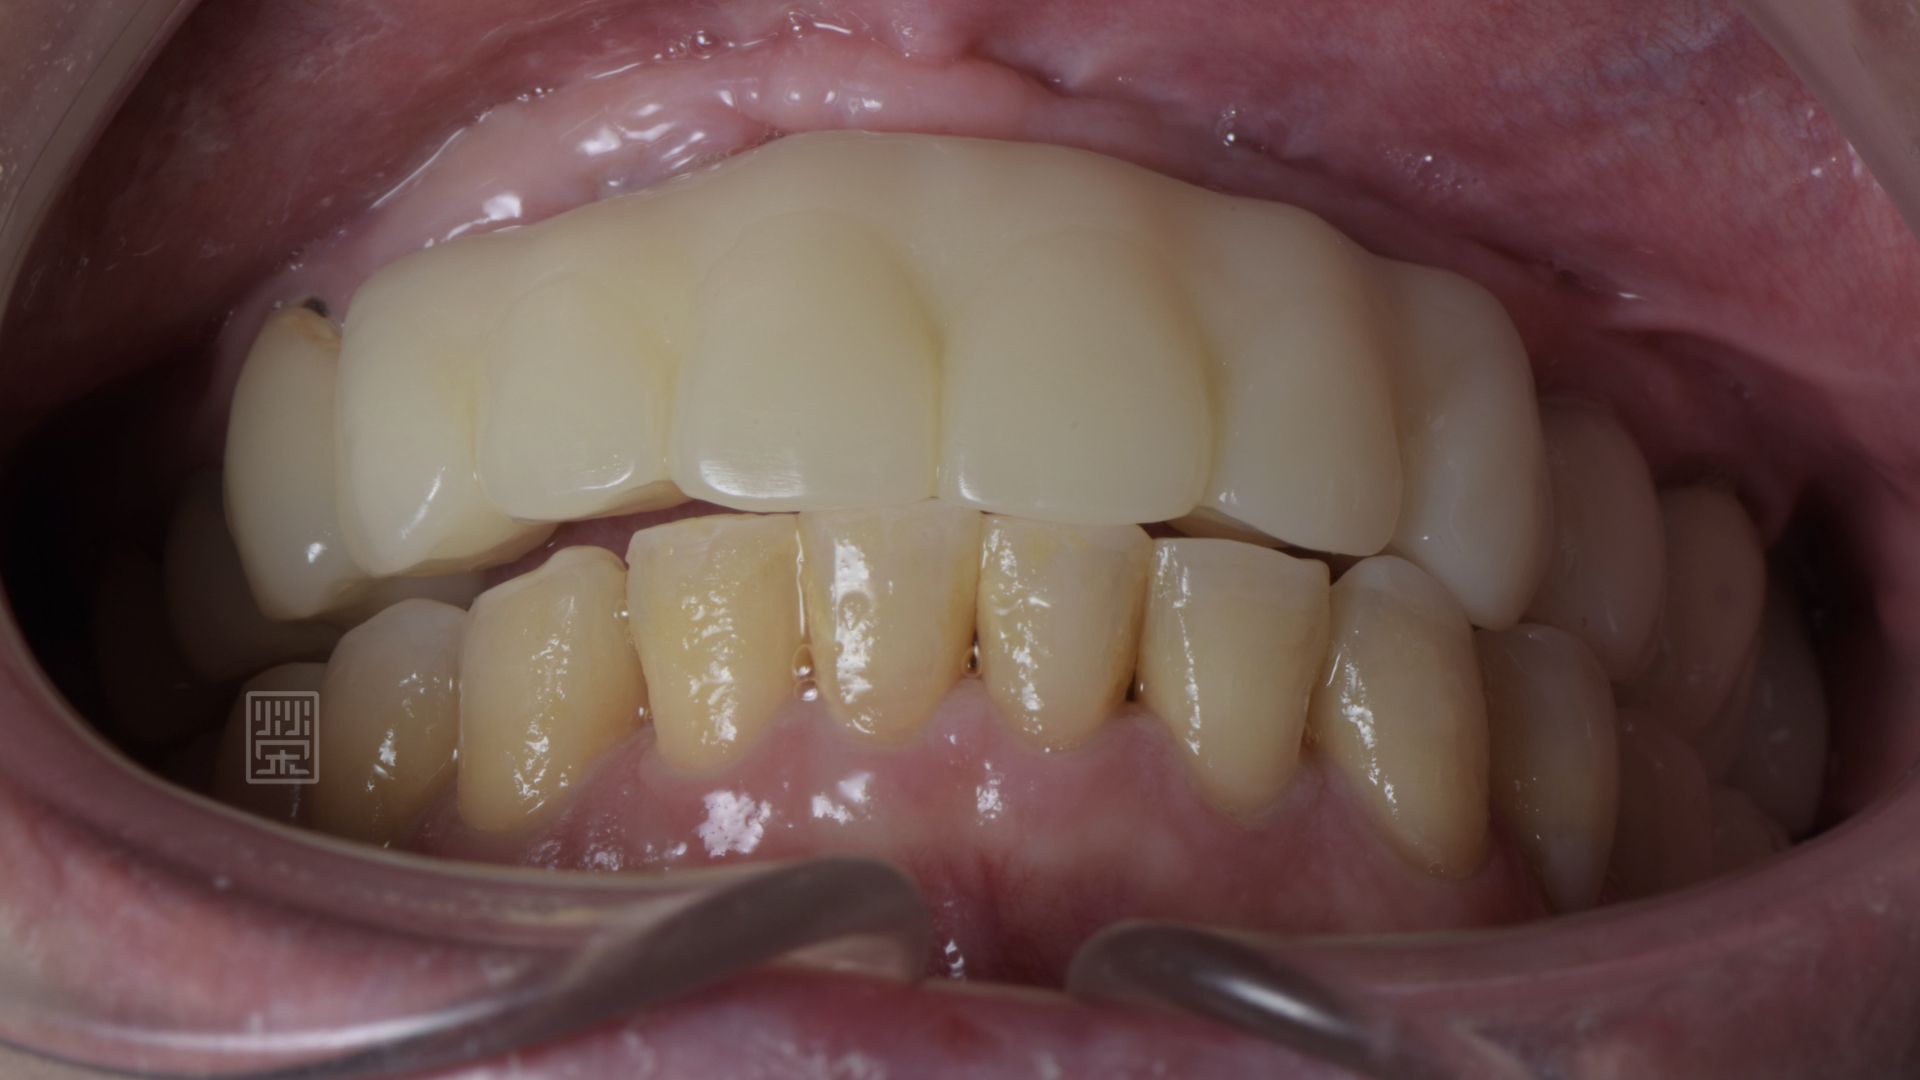

更換臨時假牙後,恢復外觀與功能

矯正後,再將門牙拉長,達到理想的牙齒的長度